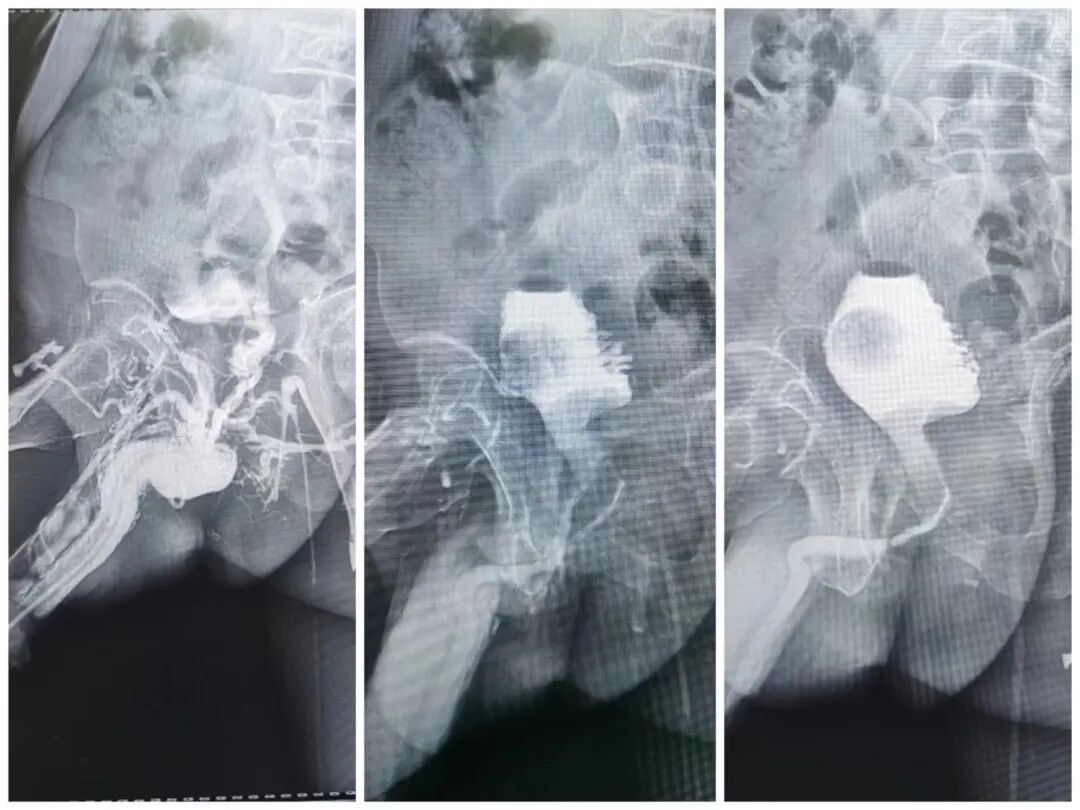

(三)下消化道造影

用于直肠、结肠及回盲部病变的造影诊断(气钡剂双重造影)。

二、特殊检查

包括静脉肾盂造影、逆行肾输尿管造影、子宫输卵管造影、瘘管及窦道造影。